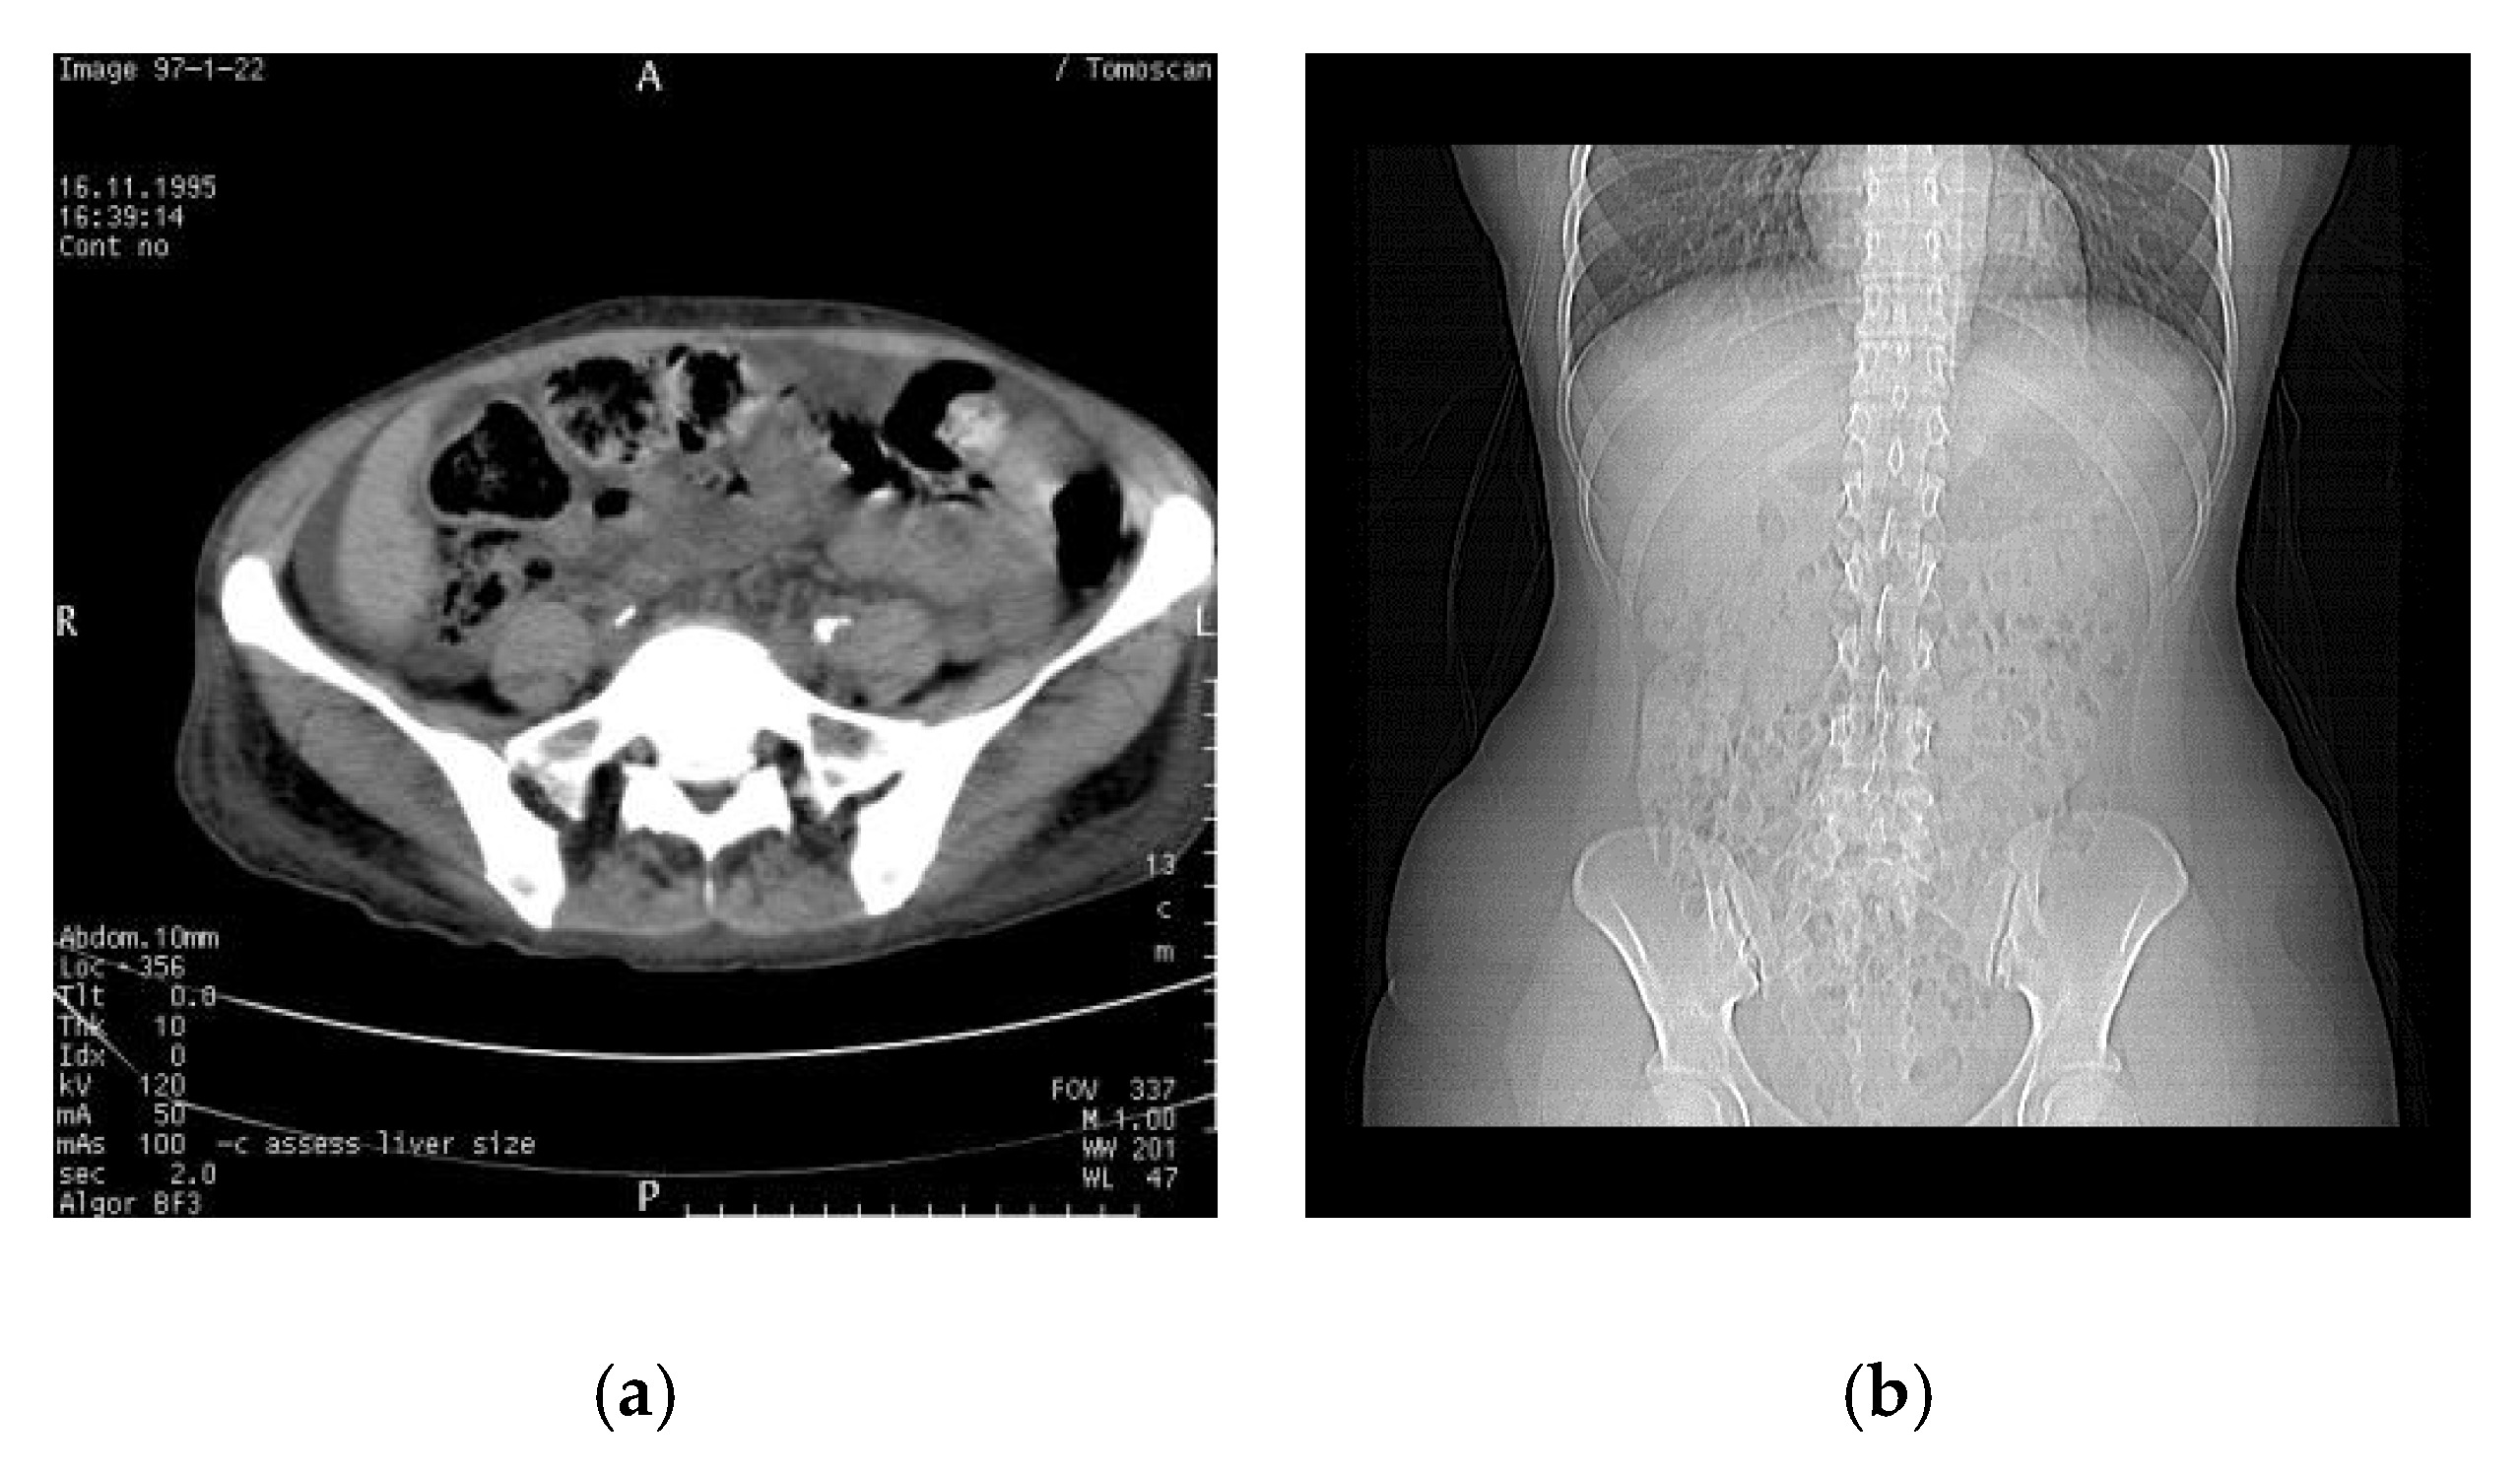

In this section, we show the actual simulation results of WMNet in the ownership authentication verification phase. Figure 4 shows the medical images used in the simulation, which are of size pixels. The medical images are computed tomography (CT) and X-ray images. Figure 5 shows the watermarks used in the simulation, which are binary images of sizes and , respectively. Figure 6 shows the simulated result using Fan’s lossless watermarking system [15] with no imaging processing damage done to the medical images by the proposed system. Figure 6a,b show the OSI and MSI generated from the CT image, and Figure 6c shows the extracted watermarks. Figure 6d,e show the OSI and MSI generated from the X-ray image, and Figure 6f shows the extracted watermarks. From the simulation results, we can see that the lossless watermarking system can correctly retrieve the watermark if the image has not been attacked by image-processing methods.

Figure 4.

Medical images used in the experiment. (a) Computed tomography (CT) and (b) X-ray.